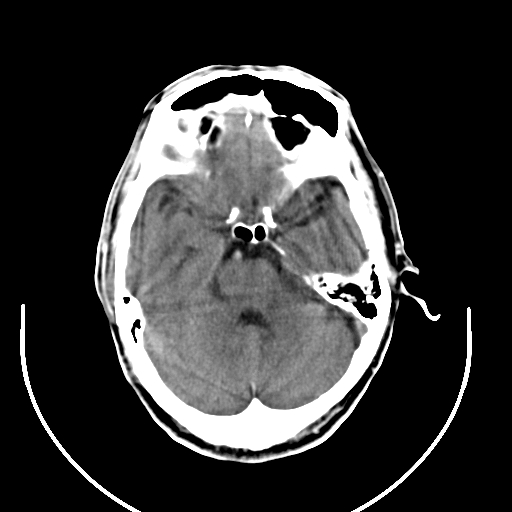

以下是引用拾荒者在2008-7-26 15:36:00的发言:[br]侧脑室内高密度钙化影,未见软组织结构,侧脑室未见增大,考虑良性钙化性改变(钙化型脑膜瘤可能)。

以下是引用宇宙ct在2008-7-26 13:43:00的发言:[br]支持:钙化性脑膜瘤。 不排除脉络膜瘤 [br] [br]